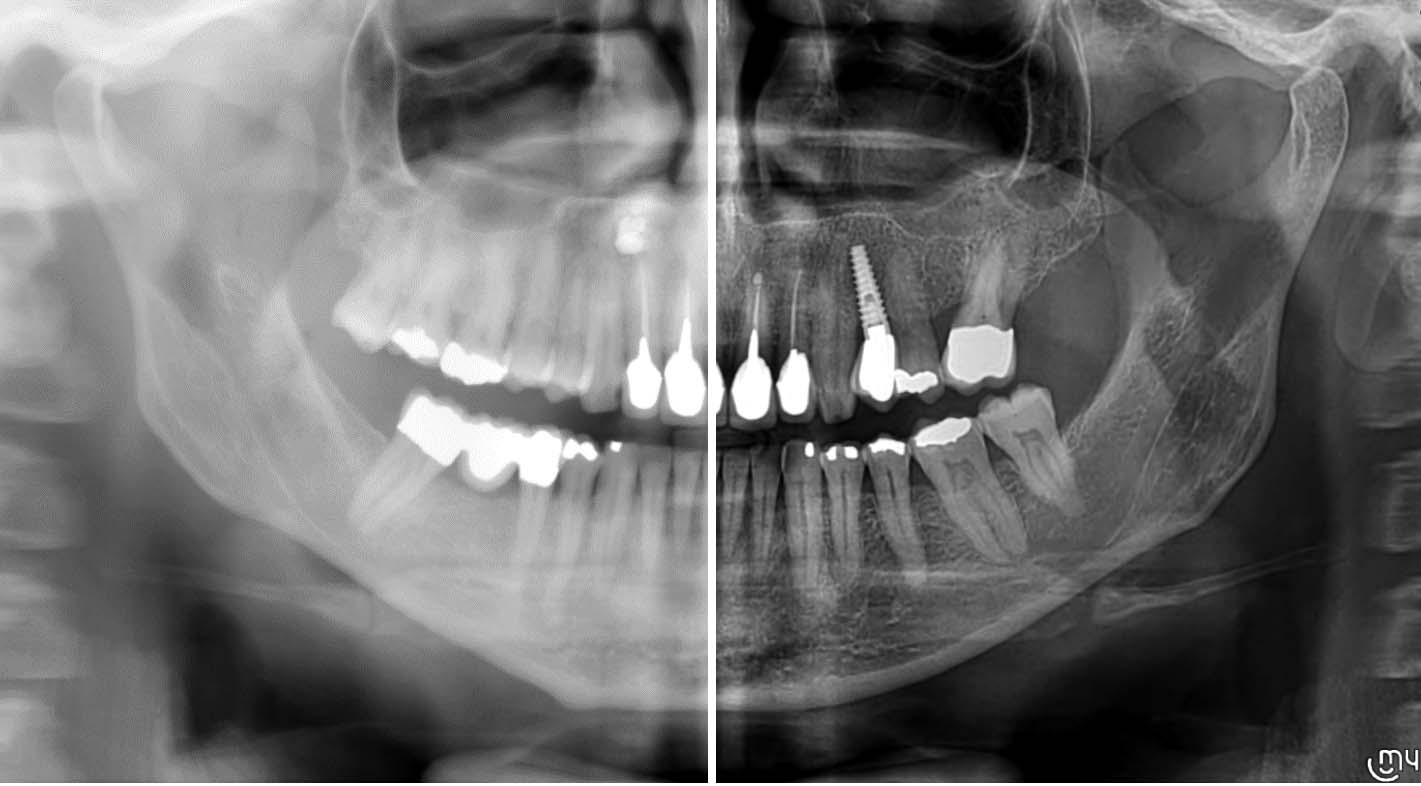

Yeni nesil hassas Cmos Flat Panel Teknolojisi. Görüntü kesitleri eskiye göre 2 kat daha keskin ve net görüntü almayı sağlamaktadır. Panoramik görüntülemede devrim yaratan Panoral 5 MultiPan çekim tekniği ile tek panoramik doz ile 5 ayrı katmanda görüntü alınır. Reel 16 bit yüksek gri skalası ile yüksek çözünürlük ve kesin tanı imkânı sunmaktadır. PANORAL 5 MULTIPAN Panoramik Röntgen Çekim Tekniği: CMOS Flat Panel Hassas Sensör teknolojisi tek bir panoramik doz ile horizontal düzlemde 3 mm. aralıkla, hastanın 5 ayrı vertikal panoramik görüntüsünün elde edilmesini sağlamaktadır. Bu şekilde net alan derinliğine girmeyen bir diş var ise bir önceki veya bir sonraki filmde görülebilir. Panoral 5 MULTIPAN görüntüleme tekniği; maloklüzyon ve hasta pozisyonlandırma hataları nedeniyle oluşabilecek görüntü bozukluklarını elemine edebilmektedir. Böylelikle panoramik röntgen çekimlerinde pozisyonlandırma hatalarına bağlı çekim tekrarlarına da gerek kalmaz.

IRYS ile 2D/3D TARAMALARININ YÖNETİMİ 2D ve 3D görüntülerin yönetimi tek bir yazılım üzerinden yürütülür. Çoklu Masaüstü sistemi, 2 boyutlu ve 3 boyutlu görünümler arasında hızlı gezinme mümkündür. Yüksek kaliteli teşhisler yapmak ve hasta ile hızlı bir şekilde iletişim kurmak için ihtiyaç olabilecek her şey IRYS yazılımdadır.